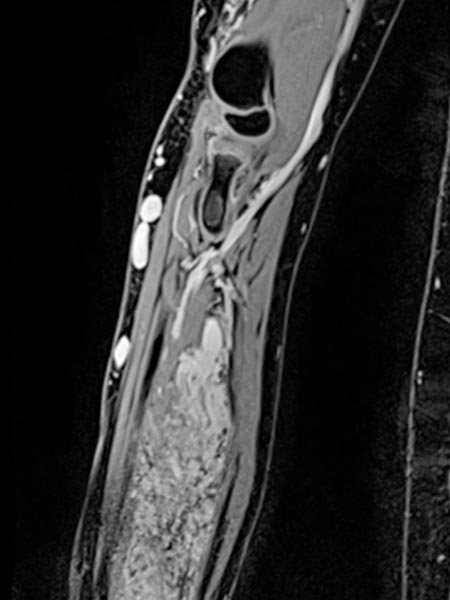

Die koronare, T2-gewichtete, fettunterdrückte Sequenz einer MRT mit Darstellung des rechten Ober- und Unterarms zeigt eine doch deutlich größere Ausdehnung der Malformation als rein klinisch vermutet.

Die Ausdehnung ist vorwiegend subfaszial in der Tiefe der Muskulatur des Ober- und Unterarms. Die Signalgebung ist stark hyperintens, somit sicher eine Slow-flow-Malformation (venös oder lymphatisch).

Die venöse Malformation zeigt in der T2-gewichteten, fettunterdrückten MRT eine tiefe Ausdehnung im Bereich der tiefen Flexorensehnen der Hand und des Unterarmes.

Am distalen Unterarm rechts im Bereich der hauptsächlichen Ausdehnung der Schwellung zeigt sich das Ausmaß der venösen Malformation vorwiegend im Bereich der Flexoren. Stark hyperintenses MRT-Signal in der T2w-Fettsättigung. Die gesamte beugeseitige Muskulatur ist durchsetzt.